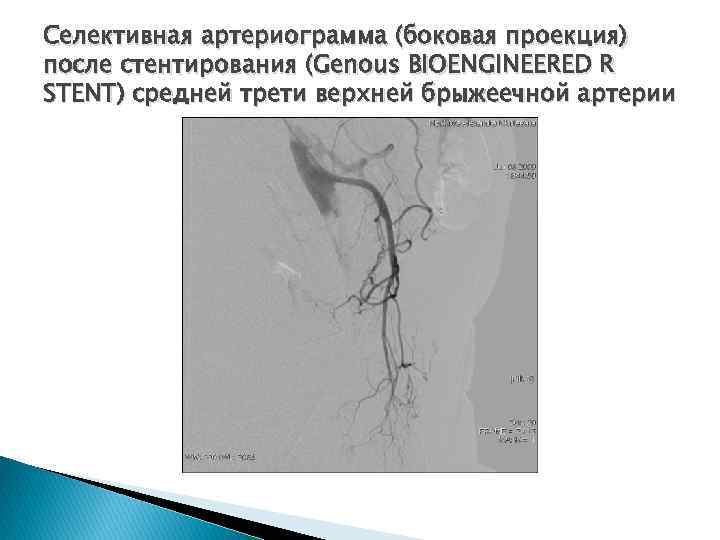

Селективная артериограмма (боковая проекция) после стентирования (Genous BIOENGINEERED R STENT) средней трети верхней брыжеечной артерии

Селективная артериограмма (боковая проекция) после стентирования (Genous BIOENGINEERED R STENT) средней трети верхней брыжеечной артерии

Фрагмент трехмерной реконструкции (3 DR) после стентирования (Genous BIOENGINEERED R STENT) верхней брыжеечной артерии

Фрагмент трехмерной реконструкции (3 DR) после стентирования (Genous BIOENGINEERED R STENT) верхней брыжеечной артерии